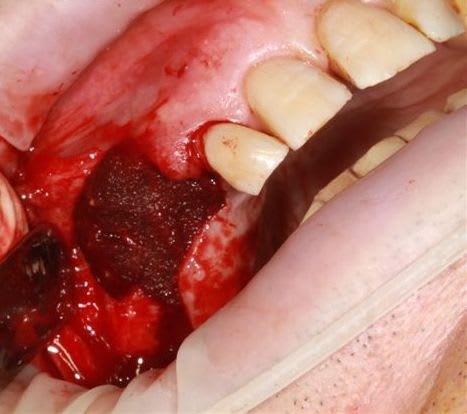

Ensuite zone 16 .. carottage, sciage en vest, carottage prélèvement de la carotte ajustage (délicat ça glisse:-)))

sur 2 ième et la troisième photo, tu utilises le disque pour pouvoir faire levier et sortir la carotte ?

Dans un premier temps oui, mais l'os etait trop "raide" donc j'ai repris la scie cloche en perpendiculaire.